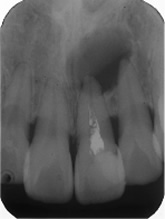

感染根管処置症例.1

主訴:2日前にかけたが、痛みやしみる症状はない。

- 被せ物を外し、過去に行った根管充填が不十分だった為、再度感染根管処置を行う。

- 1番細いファイルを使って、未治療の根の先まで到達したことを確認。

- ファイルを使って根っこの長さを測定・根管形成(根管-神経が入っていた管-を根管充填しやすい形に整えること)

- 根管充填剤が根尖(根っこの先端)まできっちりと充填されている。